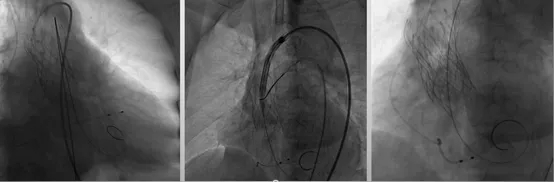

基于此,建议:(1)针对导丝跨瓣困难:可选用AL1/2导管、右冠导管或经修剪成不同角度与形状的猪尾导管,以提高导丝跨瓣能力,并在快速起搏状态下尝试导丝通过。(2)针对球囊通过困难:可应用圈套器辅助以改变主动脉根部的进入角度,同时配合使用外周小球囊进行预扩张,以改善球囊的通路条件。(3)针对瓣膜输送与定位困难:可借助圈套器调整输送路径、应用可调弯器械、配合加硬导丝预塑形及其他操作技巧,以提高瓣膜系统的稳定性和定位准确性。

横位心、重钙化TAVR

重度狭窄、钙化、高低瓣,跨瓣困难,快速起搏后增加跨瓣机会